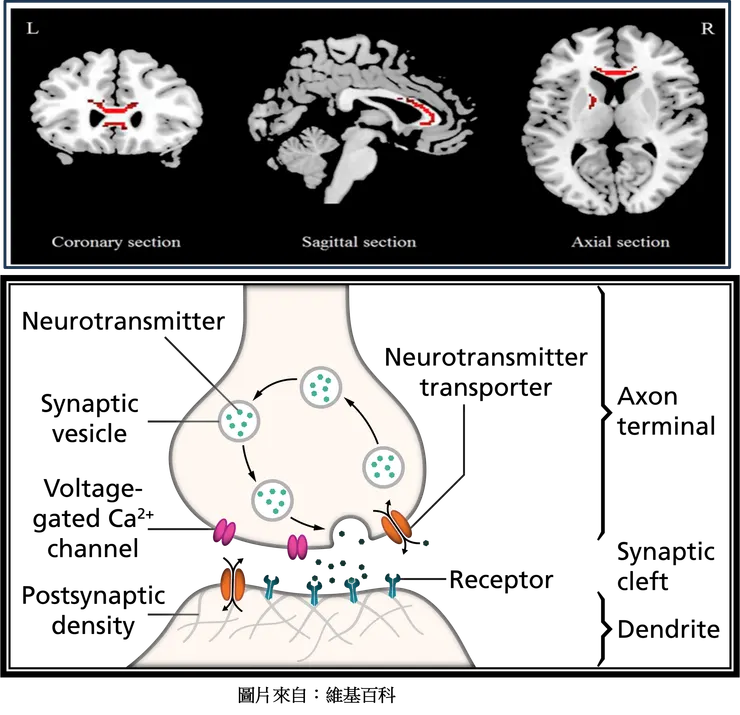

- 神經傳導物質失衡:

單胺失衡:包括腦中正腎上腺素、血清素和多巴胺等單胺類神經傳導物質的濃度有異常。

膽鹼能-正腎上腺素失衡:膽鹼能神經元與正腎上腺素能神經元之間出現失衡。

神經傳導物質的受體或第二信使系統失衡:在病患研究有看到異常的證據。

候選基因研究:關注可能在憂鬱症機制中發揮作用的特定基因,例如與血清素 (HTR1A)、血清素轉運蛋白 (5HTTP/SLC6A4) 或多巴胺受體 (DRD4) 和轉運蛋白 (SLC6A3) 編碼有關的基因。